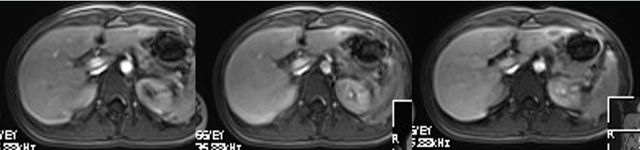

临床MR增强最常使用的对比剂为钆类对比剂,大多都是经过肾脏代谢,肝特异性对比剂可以经过肾脏及肝脏双重排谢(图1),例如:钆贝葡胺(Gd-BOPTA)、钆塞酸二钠(Gd-EOB-DTPA)在延迟后肝胆期部分被正常肝细胞吸收从胆道代谢,从而使正常肝细胞和胆道延迟强化,这个特性有助于我们对良恶性病变的判定。具有这样能部分被肝细胞吸收的对比剂就是我们所说的肝脏特异性对比剂。那么它在临床工作中又起到什么样的作用啦?我们来看看实际病例中的运用。